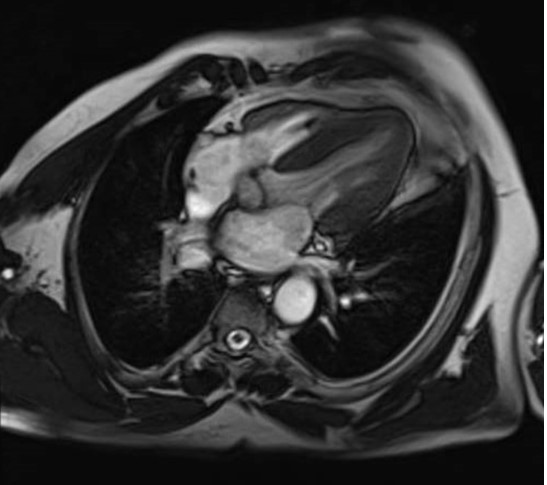

RNM Cardiaca: informa grosor miocárdico NORMAL (máximo 12 mm en segmento anteroseptal basal); tanto en cavidad derecha como en cavidad izquierda se identifican trabéculas paraseptales prominentes. Resto de parámetros dentro de la normalidad